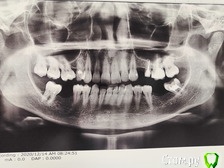

03.02.2021 на основании данного снимка(приложение) , без санации было произведено имплантация верхней 4ки.с подложкой костной ткани(название, к сожалению не знаю).Были назначены Амоксиклав, Диазолин, полоскания хлоргексидин. На второй день появился отёк без боли, на пятый появилась пульсация в области установки импланта и утек усилился. Вечером того же дня я приподнял губу и из раны вылилось много гноя.На следующий день хирург убрал швы, промыл рану, воспаление пошло на 5ку6ку.оттуда(5и6) хирург достала костную стружку. Сказала, что произошло отторжение костного материала, который утек в щель между 5-6.Назначила полоскания солью, антибиотик до 10 дней, асепта,хлоргексидин.Ежедневно в течении 6 дней я ездила к хирургу на промывание, она ставила резинки и лечила лазером. У меня были жалобы на вкус гнили после принятия чистой воды. Спустя 11 дней с момента имплантации был сделан простой снимок, хирург сообщила, что с имплантов все ок, но ей не нравится 5ка,якобы это из-за неё все.

Изначально на снимке видно ли воспаление верхних левой 5 ки и правой 4 ки?

Снимок декабрьский.

Добрый день. Разрешение приложенной картинки очень маленькое и на ней практически ничего не видно..